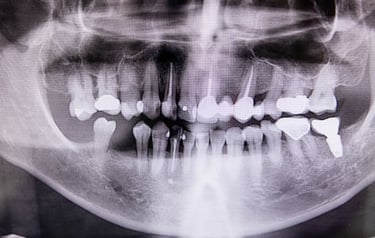

Les implants dentaires permettent de remplacer une ou plusieurs dents manquantes de manière stable et permanente.

Implants Dentaires & Prothèses Fixes